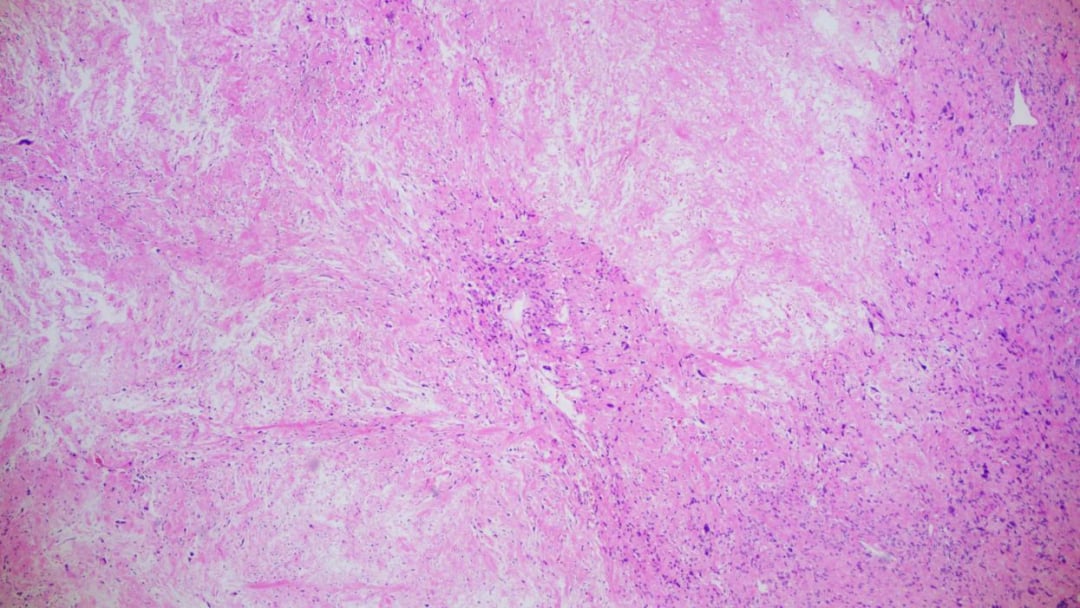

低倍镜下肿瘤边界较清晰

低倍镜下肿瘤疏密区相间

- 细胞形态多样:肿瘤组织由多种形态的细胞构成。大部分区域由交织分布的梭形细胞组成,呈现出纤维肉瘤样的外观;部分区域则呈现血管外皮瘤样结构;还有少部分卵圆形细胞围绕在骨样和软骨样基质周围。